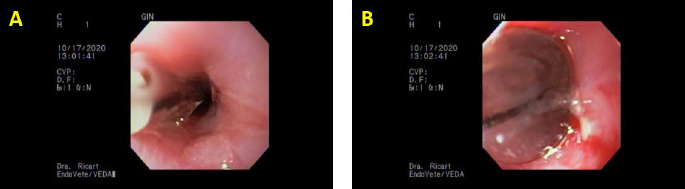

During UGE, a 7 mm annular stricture was observed 3 cm caudal to the cranial esophagus sphincter. The approximate diameter was measured by the comparison of the tip of a grasping forceps. Three balloon dilatation procedures were performed with a Boston Scientific Controlled Radial Expansion (CRE) balloon 8–10–12 mm, held for 1 minute at each diameter (Fig. 1). Between dilatations, the balloon was deflated for 30 seconds to allow mucosal reperfusion. Efficacy of the dilatation in every diameter was evaluated by macroscopic mucosal damage, drawing the attention to bleeding or tearing and intact mucosa. The endoscope traversed the dilatation with no stop at the end of the procedure. Afterward, gastroscopy was unremarkable. Anesthetic recovery was successful with no complications. The cat was discharged with indications for oral administration of 0.5 g sucralfate every 8 hours and to start oral wet feeding after 6 hours. The cat could eat soft food normally for 6 days, and thereafter it started with oral dysphagia and regurgitation; by day 10, it could only eat fluids and still had dysphagia. Another UGE under general anesthesia was performed 15 days from the first procedure with our service. A 3 mm stricture was encountered in the same place, and balloon dilatation was repeated with 6–10–12 mm diameter and a four-quadrant 0.3 ml of triamcinolone acetate 40 mg/ml was injected using a per-endoscopic needle (Disposable Injector NM-200 L, Olympus Medical Systems Corp®., Tokyo, Japan) in the submucosa.

Fig. 1. The first set of dilatations with our endoscopy service. (A) Initial dilatation with a Boston Scientific CRE balloon of 12 mm. (B) Maximum inflation of the same balloon; note the mild bleeding and tearing of the mucosa; last dilatation of that day.